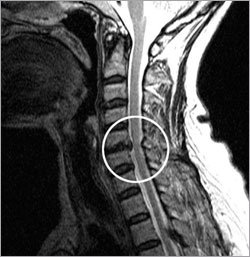

목 디스크는 목의 디스크(경추 디스크)에서 출현하는 질환으로, 경추 디스크 사이의 연골판이 터져 디스크 내부 물질이 경추 신경을 자극해 통증이나 저림증 등의 증상을 유발 해요. 목 디스크는 일상생활에서의 안 좋은 자세나 많은 운동, 부상 등이 이유가 되는 것이 될 수 있기도하고, 시간이 지날수록 발생 확률이 높아져요. 목 디스크의 증상으로는 목 부위의 통증, 팔의 저림, 근육 약화 등이 있으며, 증상이 난폭한 경우 수술 등의 치료가 필요할 수 있어요. 그리하나 대개의 경우 치료 없이도 시간이 지나면 증상이 호전되는 경우가 대부분입니다.

척수라는 중추 신경은 목뼈를 통과해 목 아래 감각과 운동 신경에 영향을 끼치기 때문에 목 디스크 증상들이 나타나면 신속하고 빠른 대처가 필요해요. 목디스크 치료형식으로 주로 초기 스탭에는 물리치료나 약물을 통해 대개의 환자들이 호전돼요. 그렇지 않다고 하면 신경 성형술과 차단술이라고 부르는 뼈주사 목디스크 치료방법을 이용하는데, 이 치료방법은 통증이 있는 신경 부위에 약물을 삽입하는 것입니다.